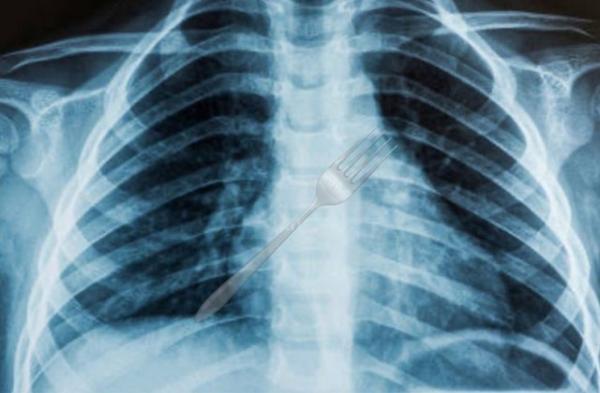

Um caso grave e inusitado assustou profissionais de saúde e moradores de Guanambi nesta sexta-feira (26). Uma mulher deu entrada, por volta das 13h30, na emergência do Hospital Geral de Guanambi (HGG), após engolir um garfo inteiro enquanto comia uma sobremesa.

De acordo com informações médicas, um exame de raio-x revelou que o talher ficou alojado no esôfago da paciente, em uma posição extremamente perigosa, oferecendo sérios riscos à integridade de órgãos internos.

Diante da complexidade do caso e da urgência para retirada do objeto, a paciente foi imediatamente regulada e transferida para uma unidade hospitalar de maior porte, em Vitória da Conquista, onde deverá passar por um procedimento especializado.

O estado de saúde da mulher não foi divulgado até o momento, mas a ocorrência chama atenção pela gravidade e raridade do tipo de acidente. A direção do HGG não informou se ela corre risco de morte, mas reforçou que o posicionamento do garfo exigia cuidados imediatos.